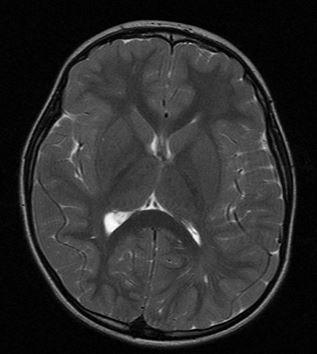

• Prueba de neuroimagen: RM cerebral.